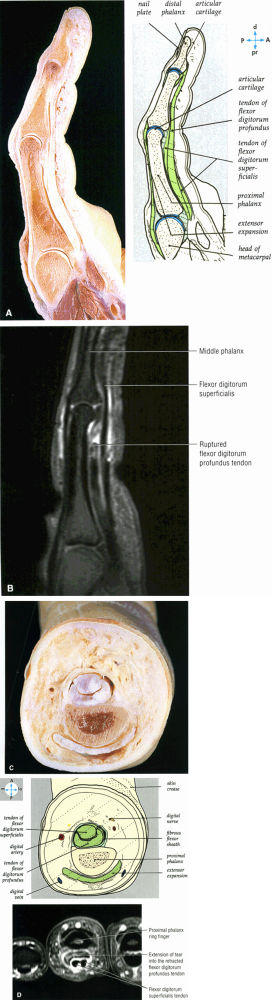

FIGURE 10.8 ● FLEXOR DIGITORUM PROFUNDUS The flexor digitorum profundus tendons flex the distal phalanges at the distal interphalangeal joints and assist in flexion of the wrist and proximal phalanges. The flexor digitorum profundus divides into four musculotendinous units in the distal forearm, and the tendons travel though the carpal tunnel deep to the flexor digitorum superficialis tendons. Distal avulsions of a flexor digitorum profundus tendon, or jersey finger, can occur when an athlete gets a finger caught in an opposing player's jersey.

|